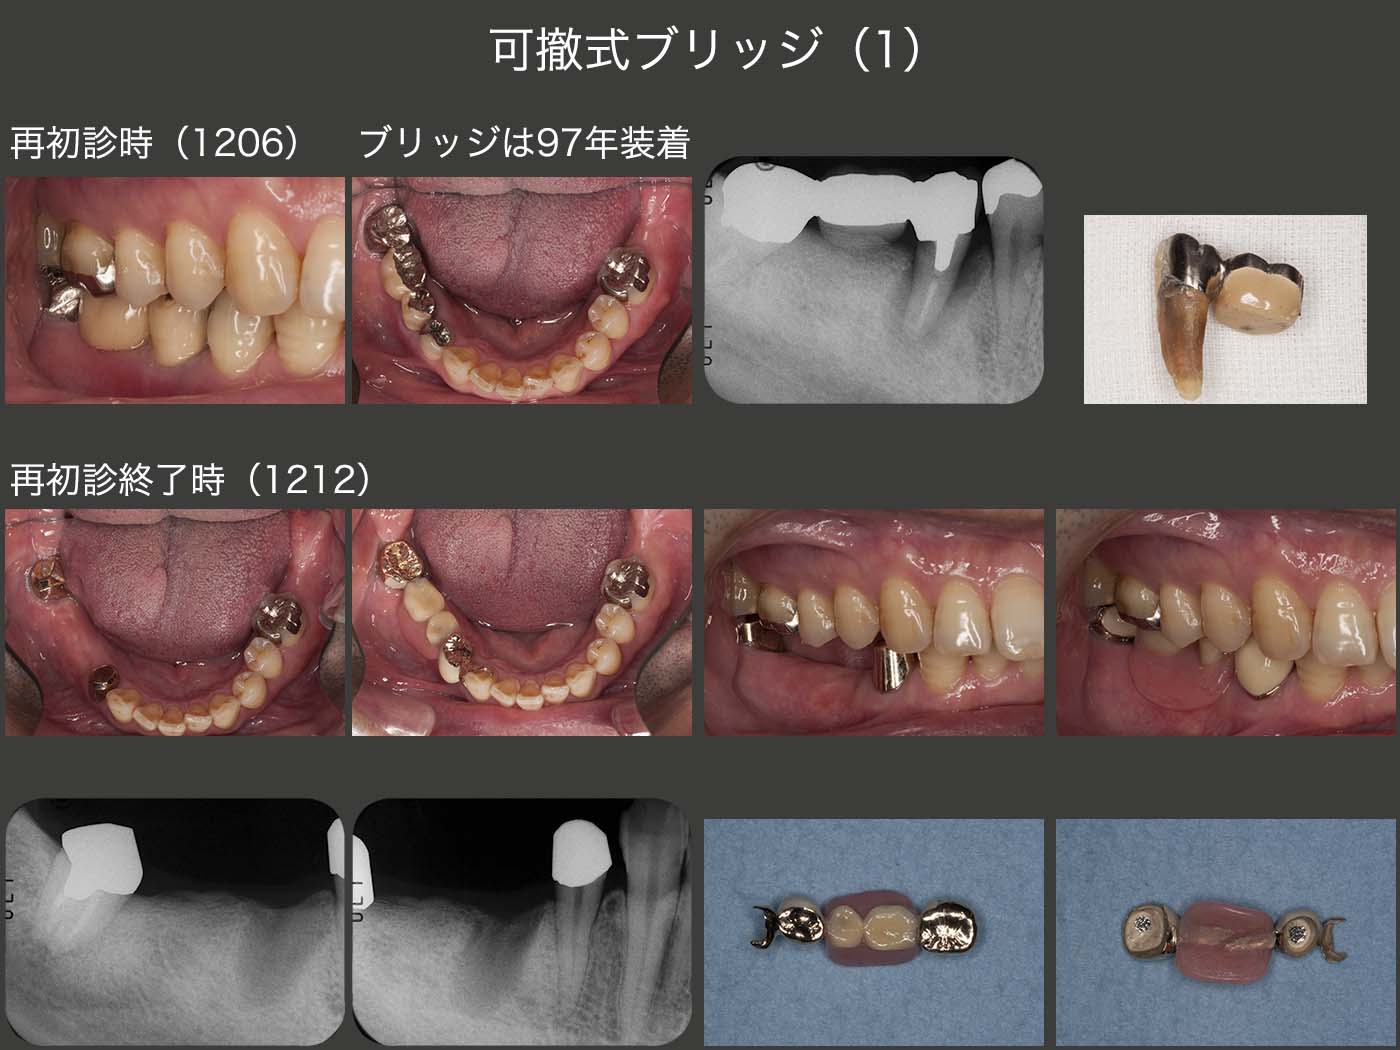

1996年初診,40歳男性.97年に右下⑦6⑤のブリッジを作り直した.特に問題なく経過したが,2012年,ブリッジ装着後15年で右下5に歯根破折が生じた.ブリッジの支台歯が無髄歯の場合に,歯根破折が生じる頻度が高い.

再度右下に,⑦65④のブリッジを装着することは可能である.しかし今回は,義歯床でも咬合力を負担させたいこと,支台歯のセメントアウトが生じる心配がないこと,支台歯の清掃が行いやすいこと,将来無髄歯である右下7を失ってもマイナーチェンジで改変できること等を配慮し,コーヌス義歯を選択した.